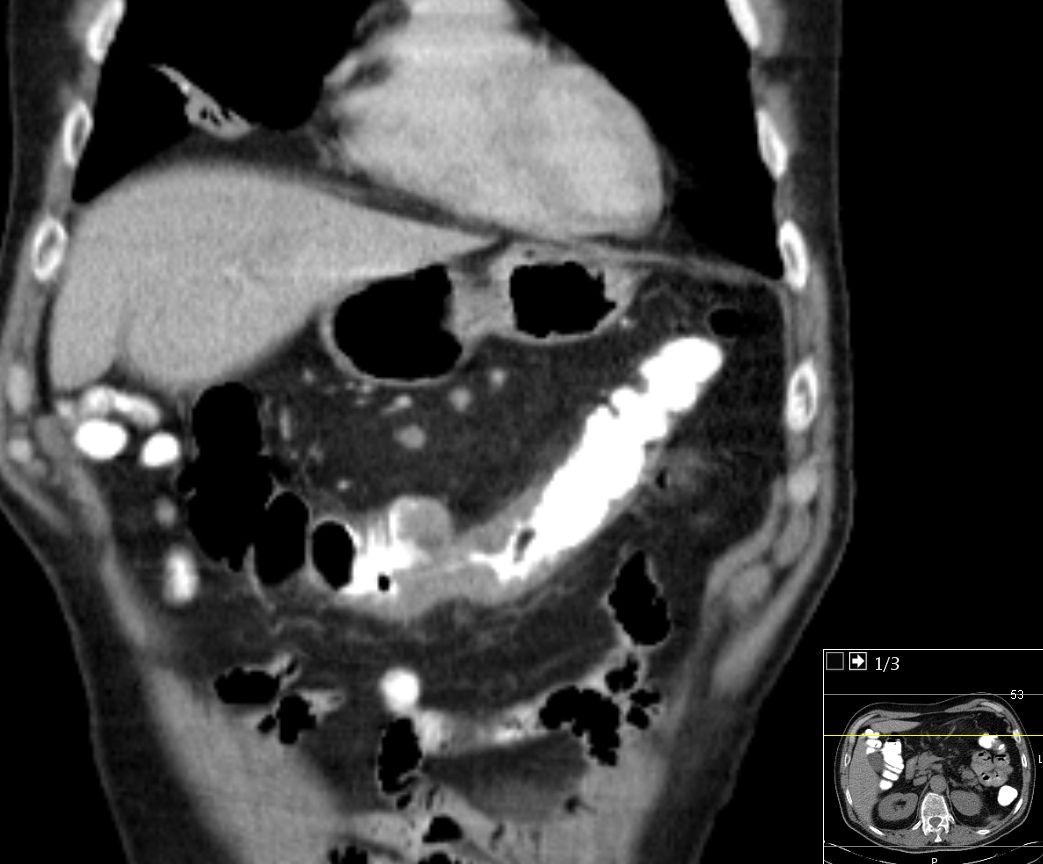

| Colon ascendens | 73-jähriger Mann mit einer Stenosesymptomatik.

Das CT zeigt einen Tumor des Colon ascendens.

Zusätzlich peritoneale und mesenteriale Metastasierung. |